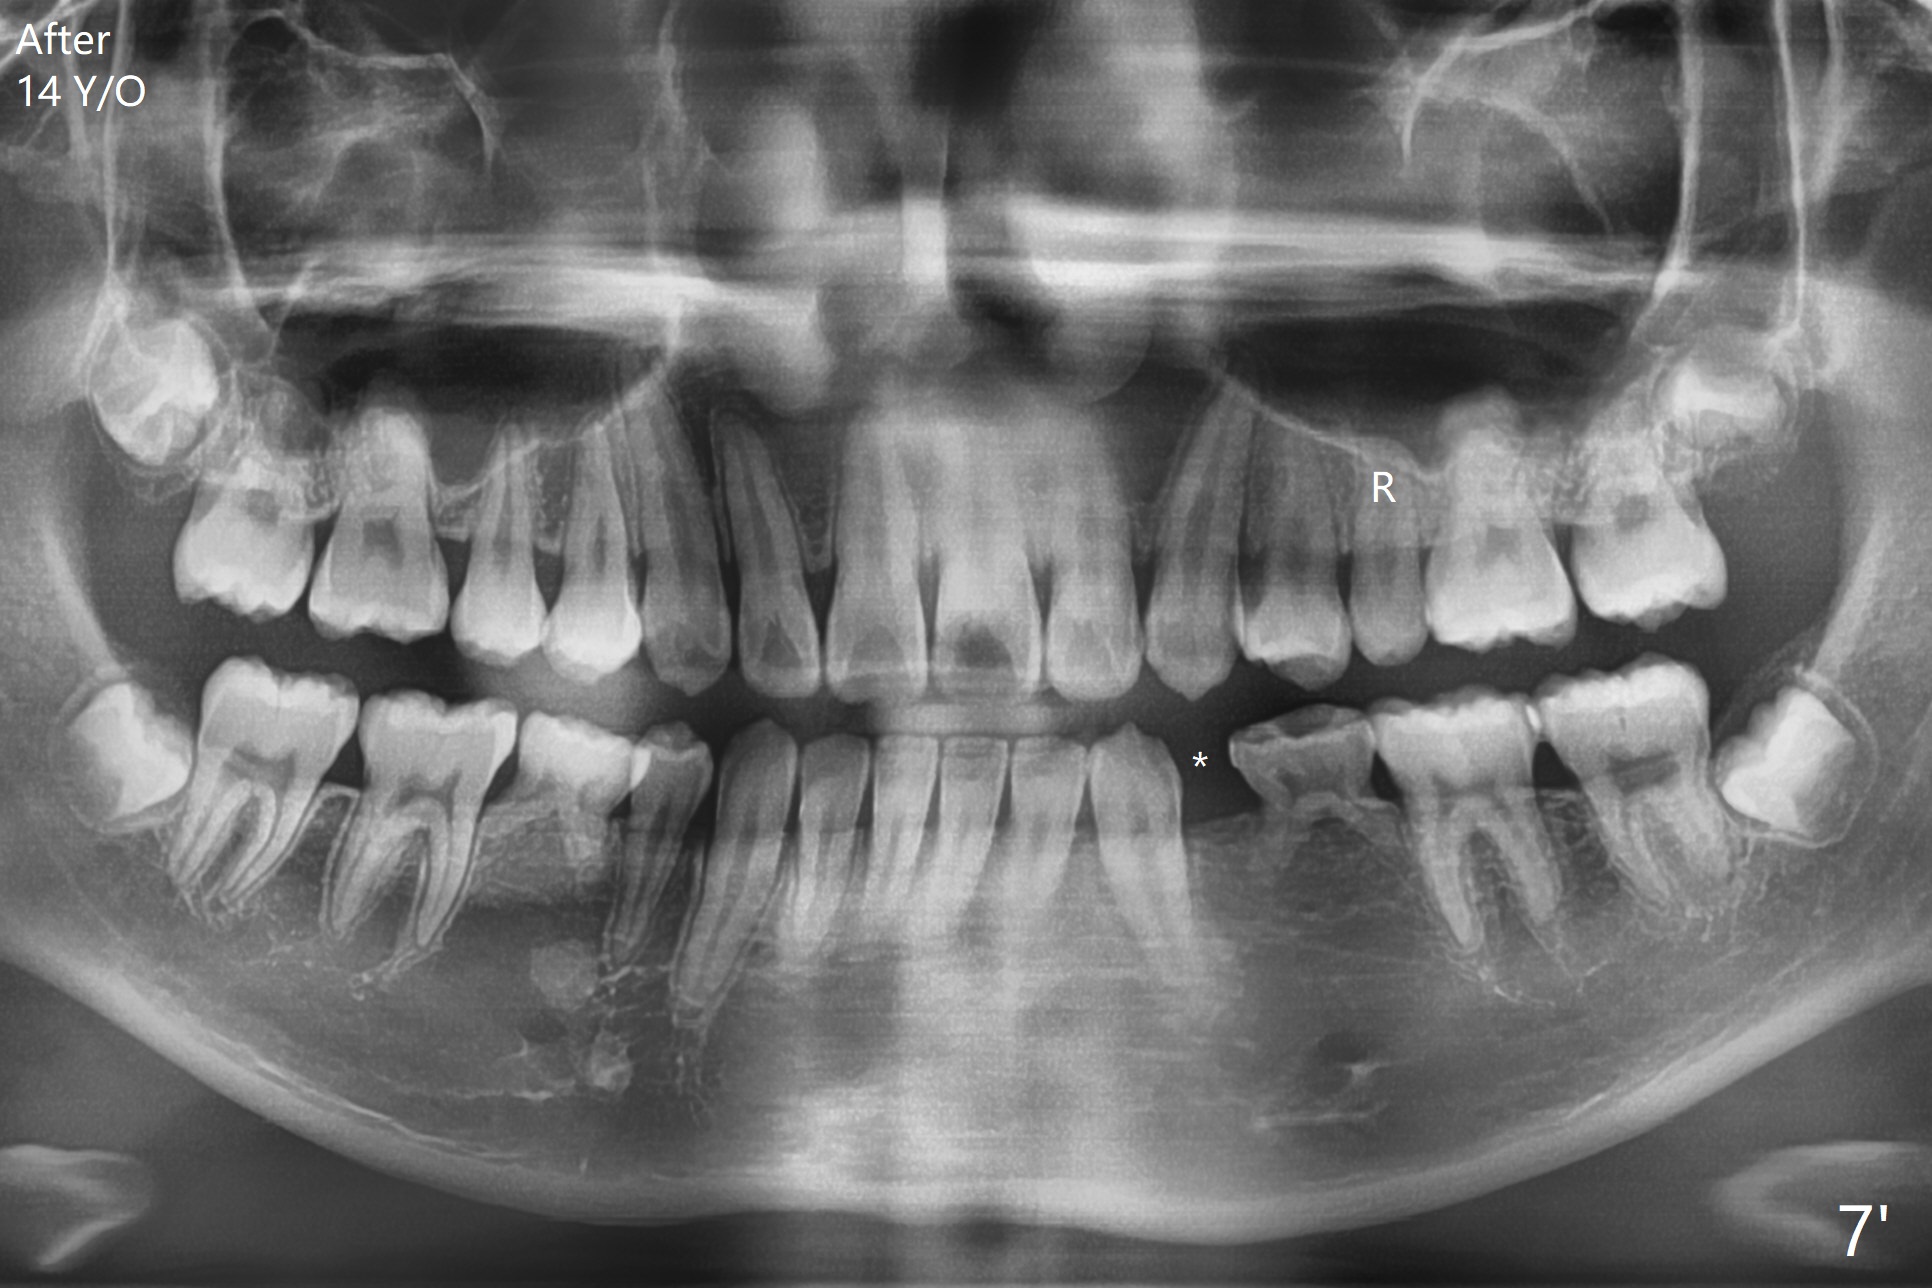

One-year-8-month orthodontic treatment reduces anterior overjet (Fig.1 (double arrows),1', with facial profile improvement), corrects right 1st molar cross bite (Fig.2,2') and dental midlines (Fig.3,3'), closes the diastema between UL3 and 4, extrudes UL5 (Fig.4,5,4',5'), and increases space for future implant at LL4 (Fig.6,6'). In fact large arches with distemata make the treatment possible! Extrusion of UL5 leads to root development (Fig.7, 7' (R)). The increased space at LL4 (Fig.7' *) appears insufficient for an implant.